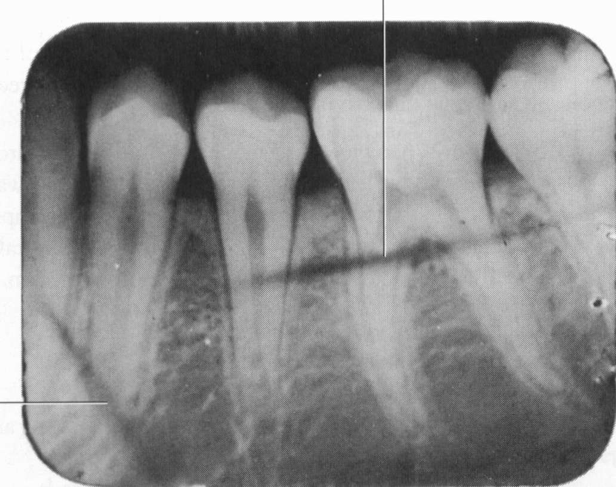

Taurodontia